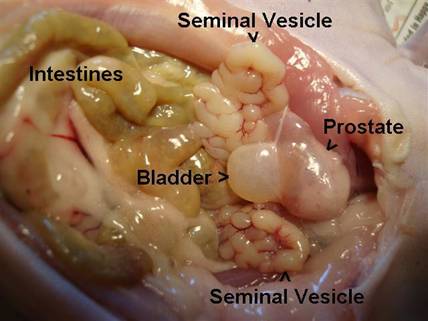

This picture, which was taken at an angle, shows the auxillary male reproduction organs.

There are 2 seminal vesicles and one prostate, which is attached to the bladder.